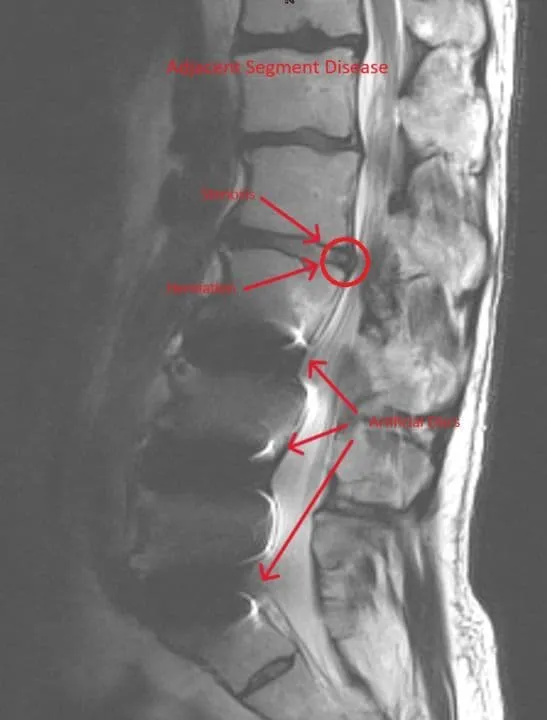

Adjacent Segment Disease

MRI of the spine showing herniation and fusion marked with arrows.

Fusion forces adjacent segments to compensate, accelerating degeneration and instability.